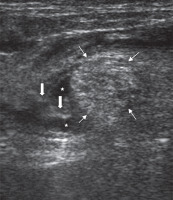

All patients underwent SNB prior to the angiography procedure. Each block was performed by an interventional radiologist (MG) who was experienced in US-guided peripheral nerve block. A posterior popliteal approach to SNB was employed in this study. The patients were placed in the prone position. After skin disinfection, an ultrasound system with a high-frequency linear transducer (9-13 MHz) was positioned to localise the sciatic nerve on the popliteal fossa. After identifying the sciatic nerve as a round, hyperechoic structure (Figure 1), the overlying skin was infiltrated with local prilocaine. A 21-gauge needle was inserted at a 45° to 60° angle to the skin and advanced slowly toward the target nerve in a plane from lateral to medial or medial to lateral direction (Figures 2 and 3). To avoid an incomplete nerve block, the needle insertion point was chosen just above the division of the sciatic nerve. After confirming that the tip of the needle was adjacent to the sciatic nerve, the block was conducted with multiple injections of local anaesthetic to create a circumferential spread around the sciatic nerve (Figure 2 and 3). In all patients, SNB was performed with a standardised mixture of 10 ml of bupivacaine 0.5%, 10 ml of lidocaine 2%, and 10 ml normal saline. The success of the block was defined as a significant relief of pain prior to endovascular treatment. If the patients were not satisfied with pain relief within five minutes, the block was repeated with the same dose of local anaesthetics. Narcotic medications were administered if required. The dose and time of administration were recorded.

Figure 1

Ultrasound image of the pre-injection sciatic nerve in the popliteal fossa. Thin arrows: sciatic nerve; Thick arrow: popliteal artery